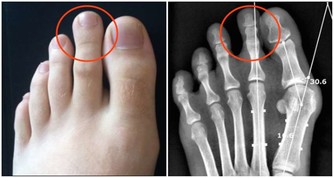

葫蘆素(英語:Cucurbitacin)是從中藥中提取,可治療肝炎及肝癌,存在於深綠色果類或果蒂部位,但誤食過量會有噁心、嘔吐、腹瀉等胃腸道症狀

人們在食用黃瓜時,因黃瓜把兒味苦而往往將其丟棄。其實,這種苦味是由其中含的一種叫葫蘆素的物質引起的,而葫蘆素C是難得的排毒養顏物質。更重要的是,葫蘆素可阻止肝細胞脂肪變性,抑制肝纖維增生,從而可預防原發性肝癌。

吃黃瓜時,一定不要把黃瓜把兒扔掉。黃瓜把兒的苦味來自其中含有的苦味素。這種苦味物質是一種葡萄甙,並認為有兩種異構體,黃瓜的苦味屬於 C型(叫做葫蘆素C)。這種叫葫蘆素C的物質,不僅存在於植物體內,而且存在於黃瓜果實的表皮內,葫蘆素C一般靠近果梗部分多,所以苦味較濃。

黃瓜中含有的葫蘆素C具有提高人體免疫功能的作用,達到抗腫瘤目的。此外,該物質還可治療慢性肝炎和遷延性肝炎,對原發性肝癌患者有延長生存期作用。